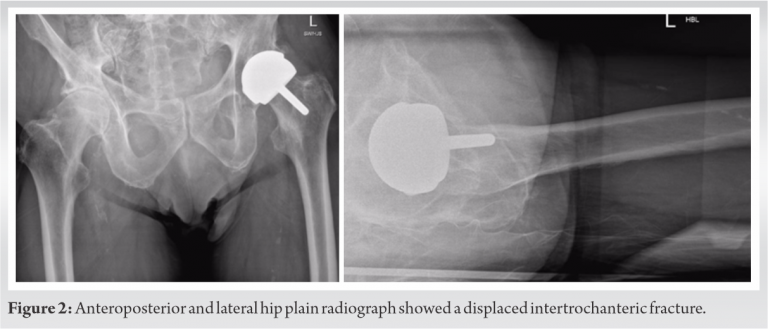

The three cases that we describe in this paper are homogenous in presentation, treatment and outcome, and therefore presented in the table below (Table 2). Pre-operative (Fig. 1-3) and post-operative (Fig. 4-6) radiographs are also included for each of the cases. 3-D reconstructed images from a computerized tomography (CT) scan for case 3 can be visualized as part of (Fig. 3).

All patients were independently mobile, active with well-fixed and well-functioning RHAs before the date of injury. All patients suffered low-energy trauma causing the fracture. All patients underwent CT scans to further delineate the fracture pattern, to assess for radiographic signs of loosening, and to assess bone stock and suitability for fixation. Intraoperatively, patients were placed on a traction table. Optimal closed reduction of the fracture was achieved using intraoperative image intensifier (II). An extended direct lateral approach to the proximal femur was used. The fascia lata was divided along its fibers and the vastus lateralis split. Fracture reduction was improved, held with 2 mm Kirschner wires placed across the fracture site, and position confirmed with II. An anatomically contoured distal femoral variable angle LCP (VA-LCP) intended for the contralateral distal femur was measured, selected, and positioned in an inverted manner (proximal and distal ends reversed). The position was checked using image intensifier. A non-locking fully threaded cortical screw was inserted distal to the fracture site to seat the plate to bone. The senior author believes that it is essential to achieve the best possible screw hold in the neck, and therefore accept to some extent that the plate distally may not sit perfectly centered over the shaft of the femur. Shaft screws can be inserted distally through a minimally invasive plate osteosynthesis technique if desired. All patients were asked to partially bear weight on the operated side for 8 weeks. The time to radiographic union and the time to discharge from physiotherapy with achievement of previous level of function were recorded for two patients. One patient, case 3 (Fig. 3, 6), was lost to follow-up as she moved out of the country.